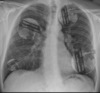

实例:51

地点:特工Belopolsky的胸腔(右肺上叶,右肺下叶,左肺上叶及左肺下叶)。

大小:直径3cm-10cm(共4个)

笔记:家庭健康护理广告。导致呼吸骤停及特工Belopolsky的死亡。根据实例51,猜想SCP-4998具有复杂的预见能力。